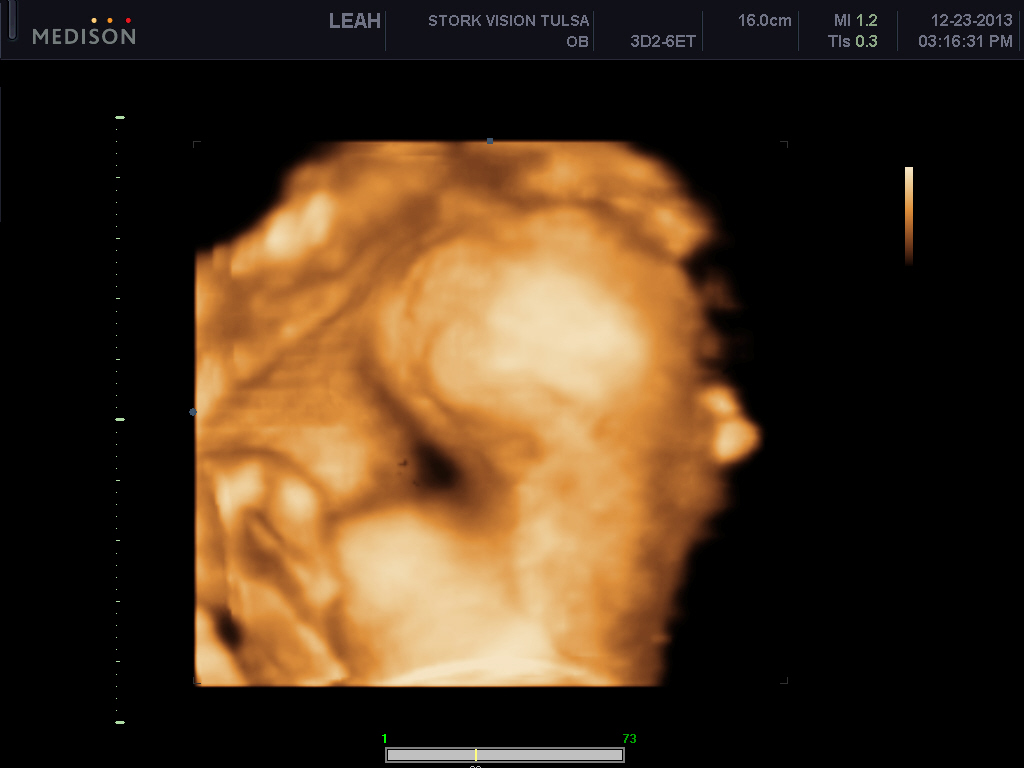

These ones below show him stretching and its just so cute to me!!